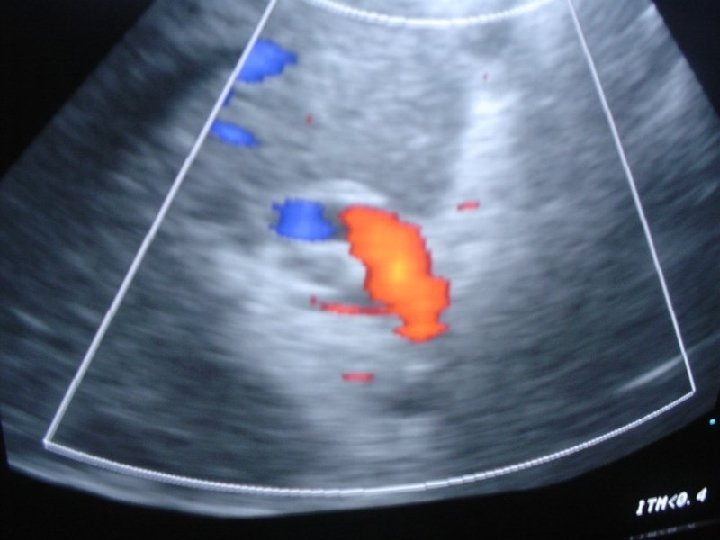

3 -D Tomografia Computadorizada Portografia

Resultados- As veias portais extrahepaticas, foram visualizadas em todos os pacientes pela 3 D- TC Portografia Nenhum desses pacientes mostrou extrahepática obstrução venosa ou transformação cavernomatosa. Todos os pacientes apresentavam uma tortuosa veia portal extrahepática em forma de N, e uma linha podia ser traçada entre as flexuras da veia portal e o hilo hepatico Nenhum paciente tinha história de Onfalite ou Cateterismo da veia umbilical

CONCEITO DO REX SHUNT MESO-LEFT PORTAL BY PASS 1 - LOCALIZAÇÃO PELO LIGAMENTO REDONDO DO FÍGADO DO RAMO ESQUERDO DA VEIA PORTA- INTRA HEPÁTICA 2 - DETERMINAR PATENCIA DO FLUXO PORTAL INTRAHEPÁTICO 3 - REALIZAR SHUNT MESENTÉRICO –PORTA ESQUERDA – JUGULAR- ILÍACA